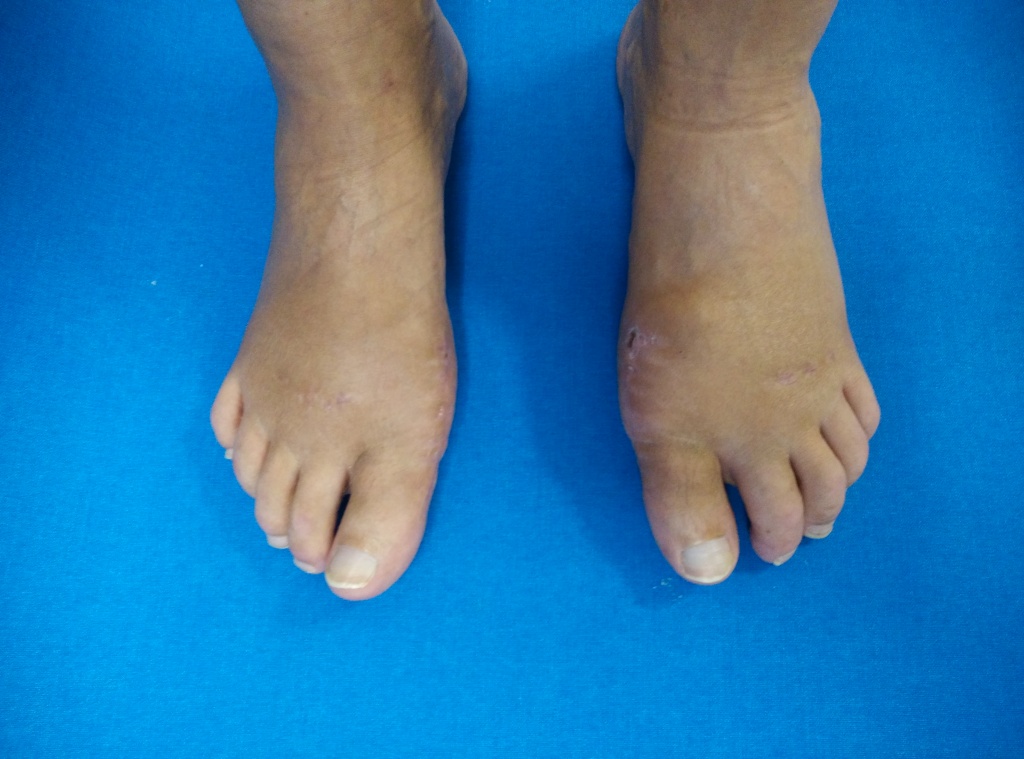

результат после устранения деформации